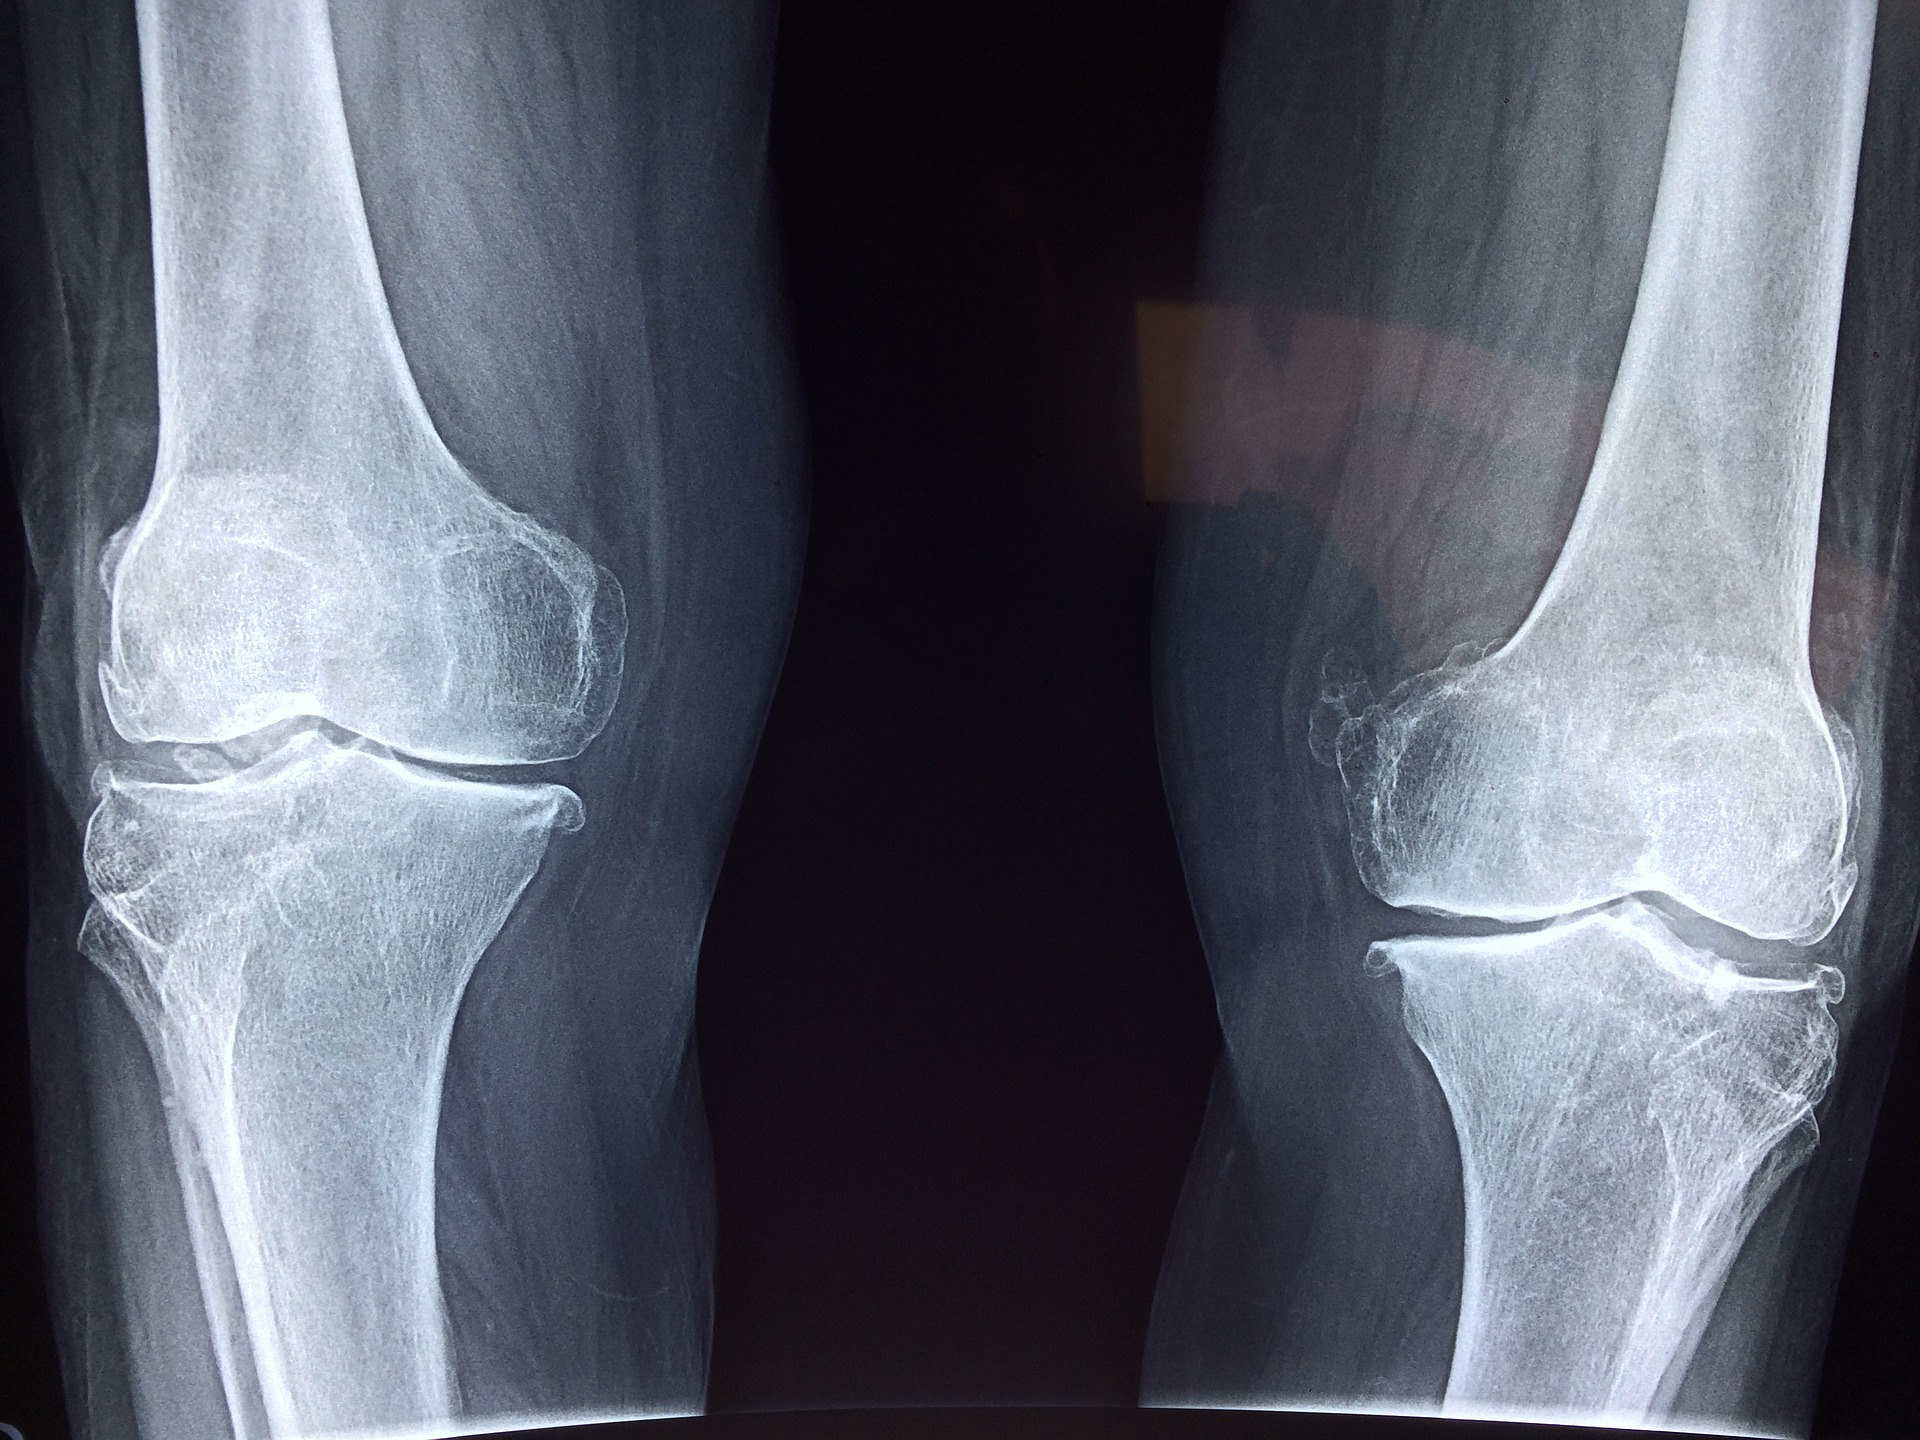

Dziś narażeni jesteśmy na bardzo wiele różnych uszkodzeń. Aktywne życie czy uprawianie sportu mogą postawić …